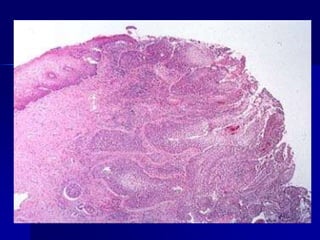

Carcinoma escamoso

invasor.

Imagen microscópica a mediano aumento de un carcinoma escamoso invasor.

Obsérvese la presencia de nidos de márgenes irregulares, rodeados por estroma

desmoplásico. Dichos nidos están formados por células atípicas, con diferenciación

escamosa. Focalmente se evidencia alguna disqueratosis. Tinción de H-E,100X.

Carcinoma escamoso invasor. Imagen microscópicaa mediano aumento de un carcinoma escamoso invasor. Obsérvese la presencia de nidos de márgenes irregulares, rodeados por estroma desmoplásico. Dichos nidos están formados por células atípicas, con diferenciación escamosa. Focalmente se evidencia alguna disqueratosis. Tinción de H-E,100X.